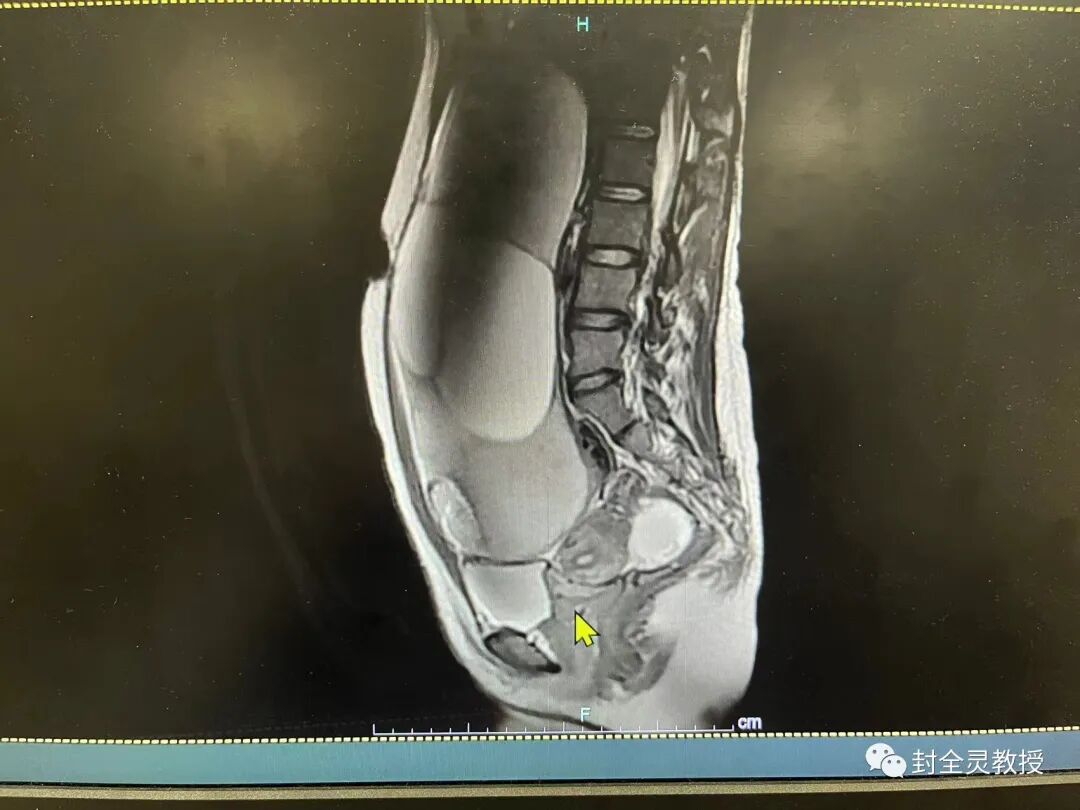

MRI:子宫后倾,形态受压体积较小,结合带完整,宫颈管存在,前后唇无增厚及异常信号;阴道无异常,腹盆腔似可见两团块状混杂长/短T1长T2信号影,T2以不均匀高信号为主、内可见斑片状低信号,并可见多发网状分隔,较大者位于子宫前方,大小约为215.9mm×83..5mm(左右径×前后径X×上下径),较小者位于子宫右后方,大小约为69.8mm×57..3mm(左右径×前后径×上下径),边界清;盆腔及双侧腹股沟未见明确肿大淋巴结。

诊断∶1.腹盆腔囊实性肿块,考虑畸胎瘤可能;2.盆腔积液∶建议结合临床。